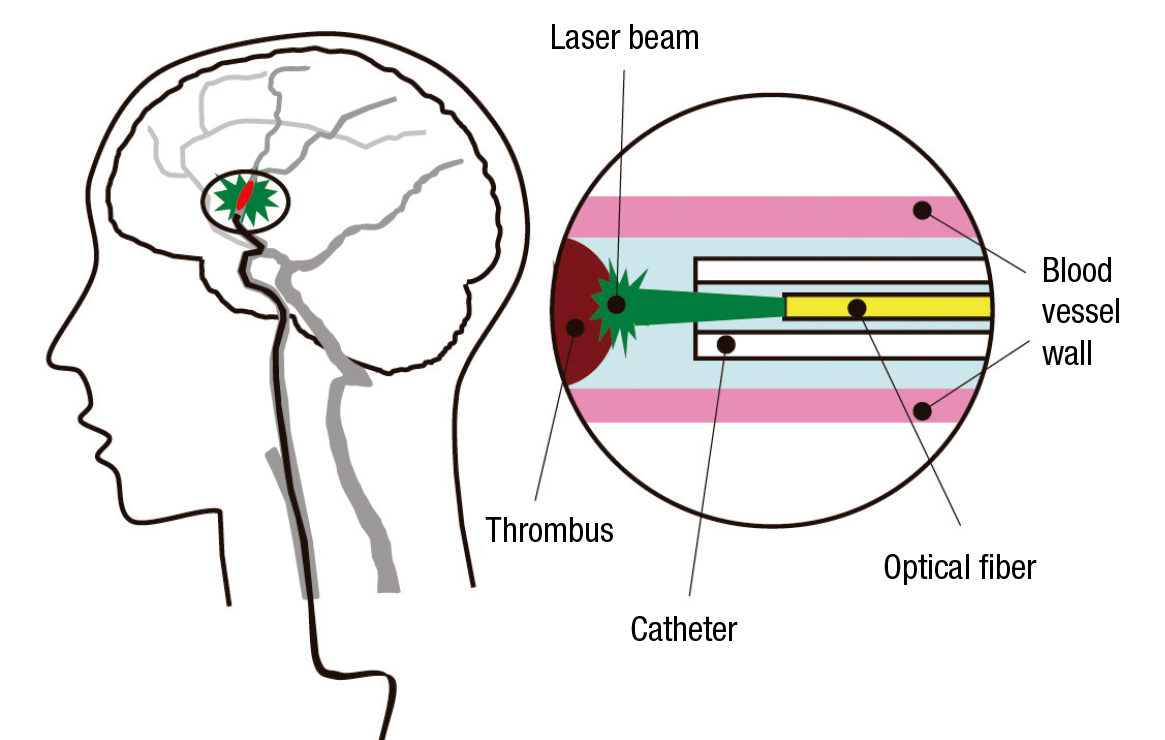

Hamamatsu Photonics has also developed many world-class products in the field of lasers, in which it started R&D activities in the 1990s. Recently it became the first in the world to develop a laser thrombolysis technology for treatment of cerebral thrombi—blood clots in the brain that cause strokes—which works as follows: A catheter encasing an optical fiber is inserted via a femoral artery and extended to the location of the thrombus, and a green laser beam at a wavelength of 532 nanometers is directed at the site. At this wavelength, the beam is not absorbed by the blood vessel wall but affects only the thrombus, which it dissolves with almost no risk of damage to the blood vessel walls. Since the tip of the catheter is thin, with a diameter of only 0.8 millimeters, and flexible, it can be used for treatment in blood vessels of around 1 mm in diameter, which are hard to treat with existing devices for suction-purpose catheterization. In this way it offers hopes for expanding the scope of cases that can be treated.

The tip of the catheter is a mere 0.8 mm in diameter.